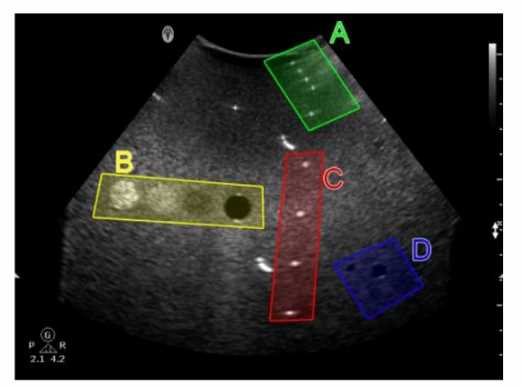

Which target group in this image of a tissue-mimicking phantom is used for gray-scale evaluation?

1. Option A

2. Option B

3. Option C

4. Option D

Answer(s): C

Explanation:

Gray-scale evaluation in a tissue-mimicking phantom involves assessing the uniformity and accuracy of the gray-scale representation of the tissues.

Option C typically contains structures designed to test the machine's ability to accurately depict varying levels of echogenicity, which is essential for proper gray-scale evaluation.

This area will have a range of echo intensities that help in determining the contrast resolution and the ability of the system to distinguish between different tissue types based on their gray-scale values.

Reference:

ARDMS Sonography Principles and Instrumentation guidelines on tissue-mimicking phantoms and image quality evaluation.